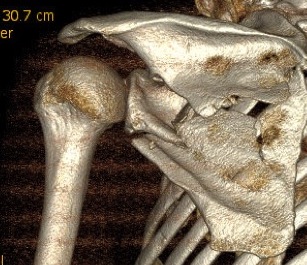

Glenoid fracture + lateral clavicle fracture + acromial fracture